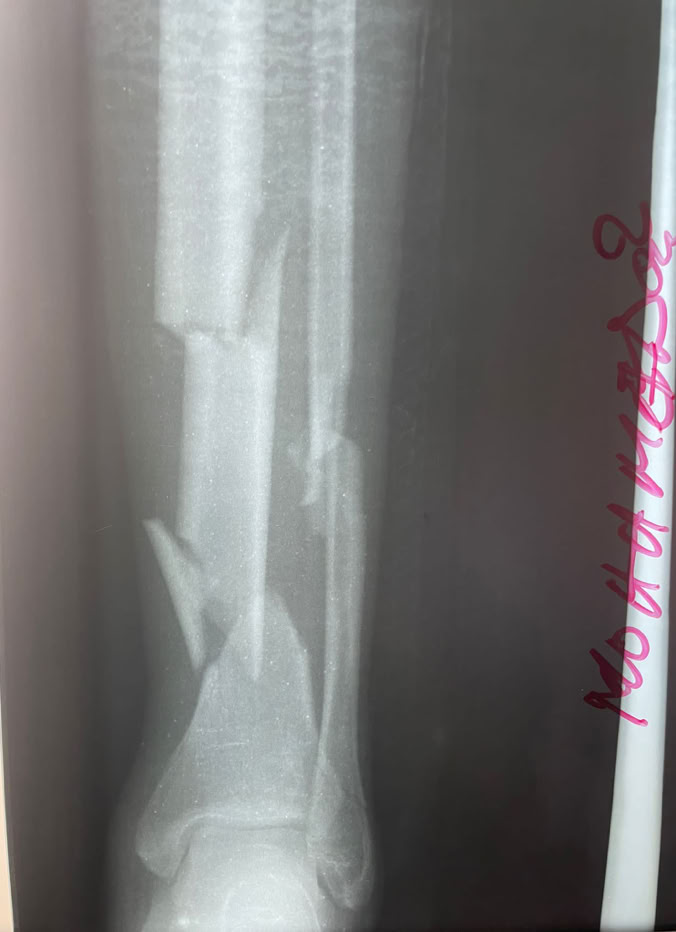

Las sesiones quirúrgicas se han podido dividir entre todos los integrantes pudiendo llevar a cabo a dos quirófanos varias cirugías entre ellas un caso complejo de fractura luxación de cadera con tibia bifocal homolateral consecuencia de los tan frecuentes y graves accidentes de moto.

En la consulta se fue fraguando lo que iba a ser nuestro quirófano a lo largo de la estancia pudiendo comprobar que la situación endémica de fracturas de tibia en todas sus modalidades continua sin cambiar. En total se han realizado 23 cirugías entre las que cabe destacar el caso anterior, ademas de 5 seudoartrosis de tibia, dos fracturas de fémur, una fractura luxación Lisfranc, de radio, seudoartrosis de humero y varios casos de cirugía de mano y miembro superior pues nos acompañaba el Dr. Galan . Ademas se han realizado varias limpiezas quirúrgicas de osteomielitis, osteítis y movilización séptica de una PTC, injertos de piel y un solo caso de ortopedia infantil de un Blount, realizado por el Dr. Nges. Poco a poco la autonomía para la resolución de los casos es mayor por parte del equipo local sin dejar de introducir nuevas técnicas como el enclavado humeral.